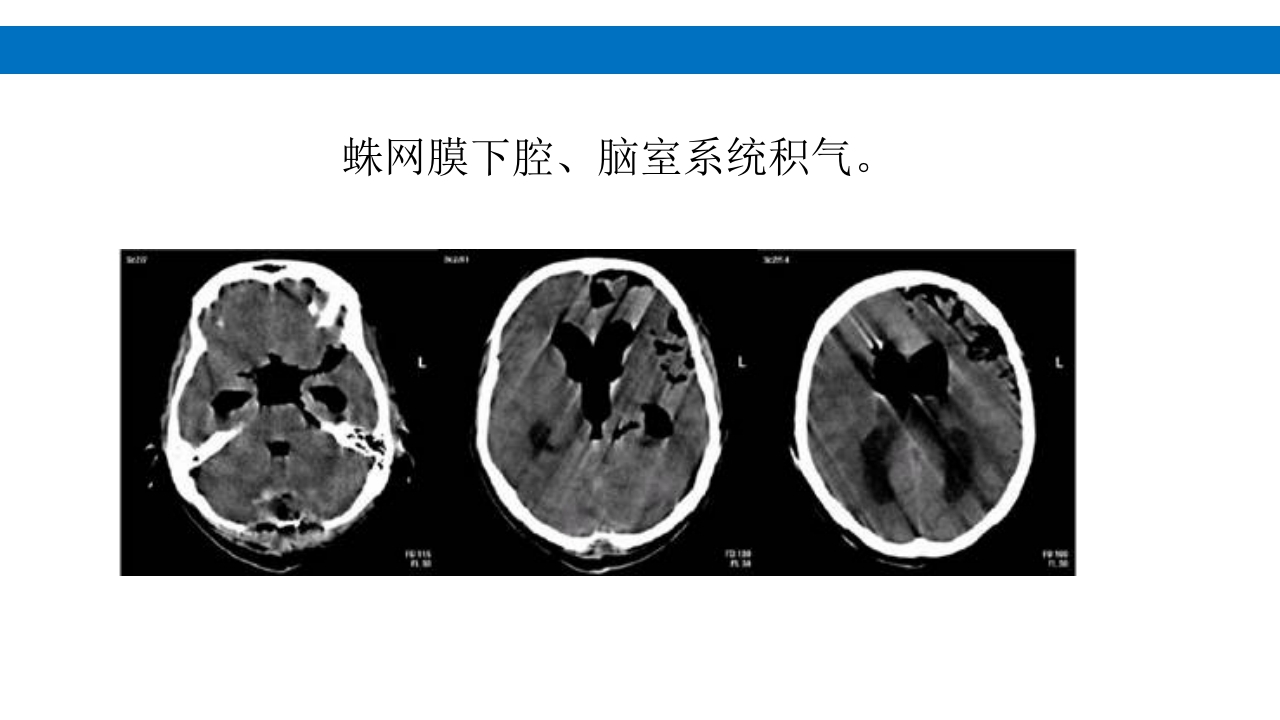

颅脑损伤的并发症及后遗症 讲解人:xxx 20XX年x月x日 1.颅骨骨髓炎 病因:为头皮软组织、中耳、乳突和副鼻窦等处炎性感染而经导 血管侵入颅骨内或颅脑开放伤感染所引起,亦可由菌血症后发生 的细菌栓子由血运转移至颅骨内。 影像学表现: 头部CT: 1.表现为不规则的蜂窝状骨质破坏区,主要位于板障,亦可累 及内外板。 2.破坏区内可见高密度的米粒状细小的高密度死骨。 3.周边可见骨质硬化增生,颅板外无骨膜反应。 4.局部的头皮可见软组织肿胀。 头部MRI: 由于受累部位细胞成分和水量增多,T1WI为低信号, T2WI为高信号,急性期边界不清,慢性期病灶局限, 边界清晰。MRI显示骨质破坏没有CT效果好。 治疗: 除应用抗菌药物控制感染外,当感染局限或已有死骨形成后, 应行手术切除感染...